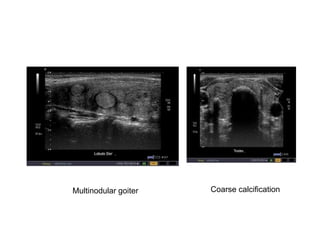

Thyroid gland

Homogenous Heterogenous

Multinodular goiter Coarse calcification